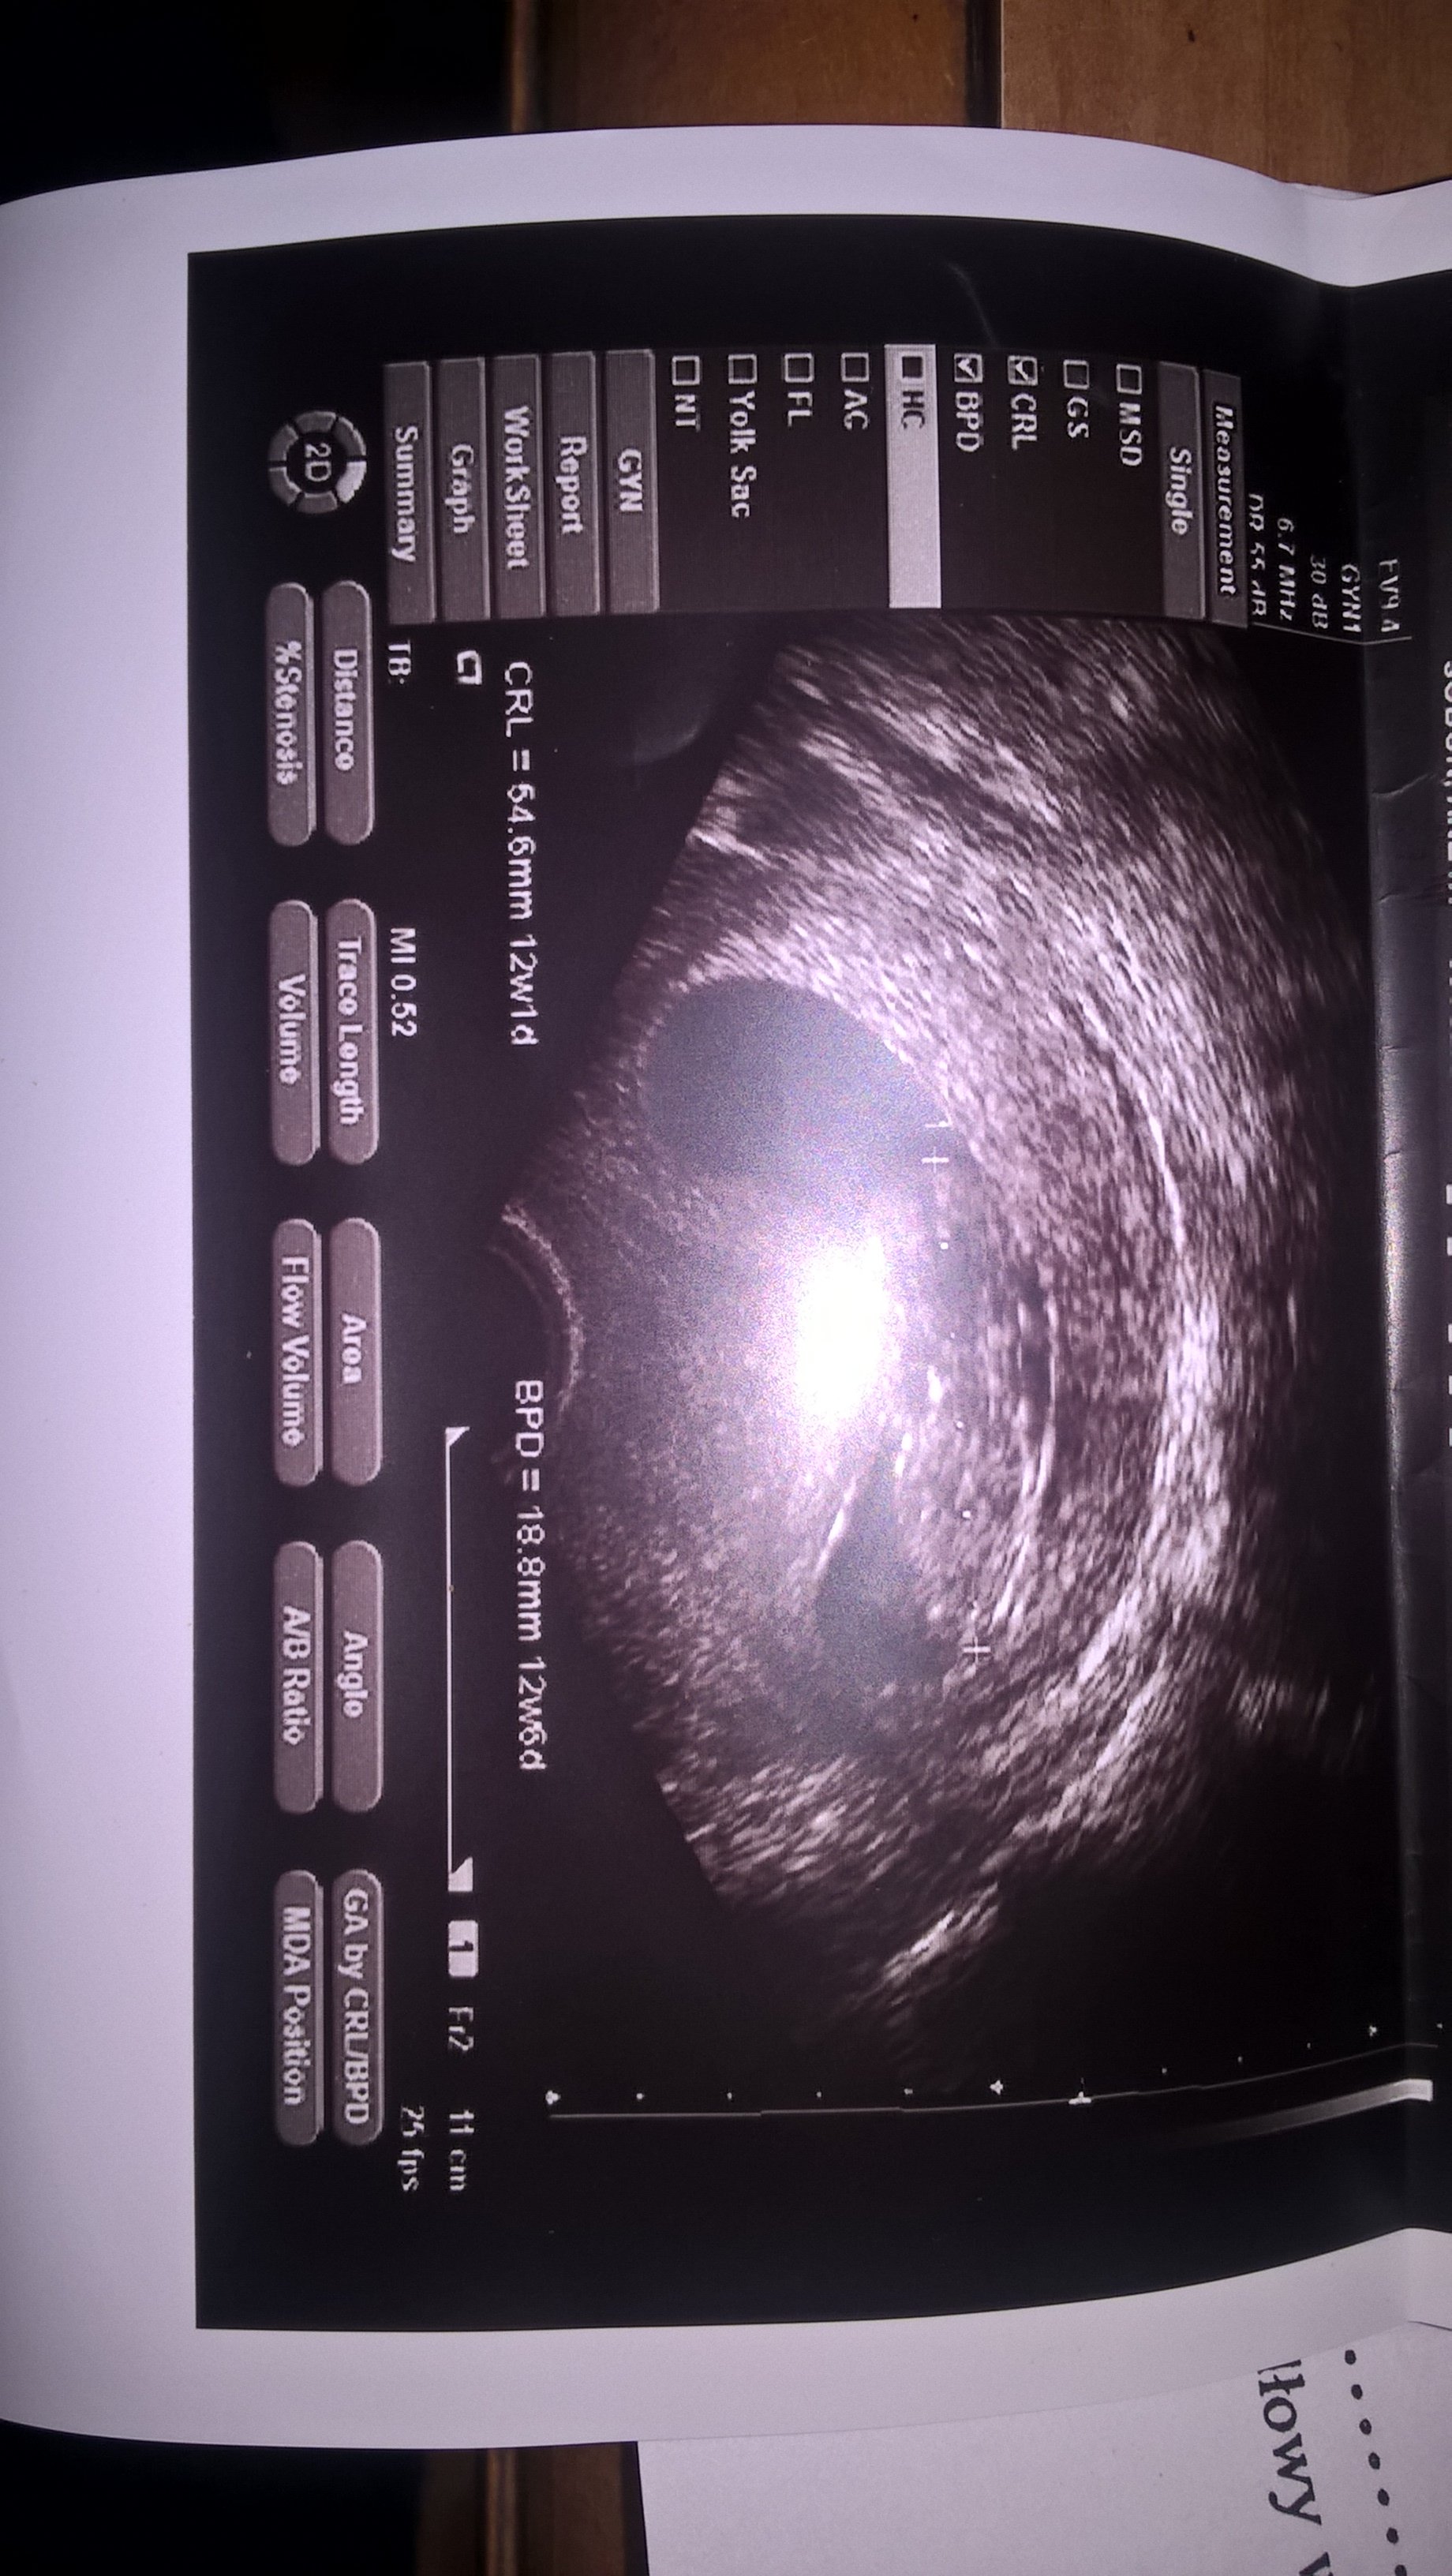

Dziekuje dziewczyny za kciukasy. Jestem po wizycie i powiem Wam ze jak zobaczyłam małego czlowieczka to sie zakochałam. Lekarz pomierzyl dlugosc .glowke i tyle:( nic nie mówił.z nim nie da sie gadac.wypisal parametry na karteczce i z tym musze sie zgłosić do swojej lekarki jutro.musze za jakis czas iść prywatnie- wiem ze z chłopcami prywatnie dokladnie mi wszystko pomierzyli .kosc nosowa otp. Tu nic- państwowo:( nawet nie wiem czy wszystko ok

to moje zdjęcia i opis

Załączniki

• WP_20170828_15_25_06_Pro.jpg

WP_20170828_15_25_06_Pro.jpg

730,4 KB · Wyświetleń: 103

z pierwszym chodziłam prywatnie i nie byłam zadowolona.z drugim na nfz ale dodatkowo usg robiłam prywatnie.i teraz tez usg bede robić prywatnie a te na nfz beda dodatkowe.czy ja dobrze widzę czy dziecko ma 12t 1dzien czyli wypadaniejsze